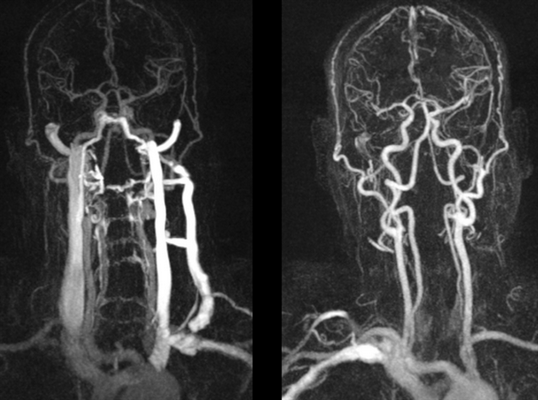

МРТ сосудов шеи что показывает

МРТ сосудов шеи или МР ангиография - метод диагностики, предоставляющий исчерпывающие данные о состоянии кровеносных сосудов в области шеи. Поскольку нарушение кровообращения в них оказывает непосредственное влияние на количество поступающей в головной мозг крови, а также кровоснабжение шейного отдела позвоночника, это может привести к серьезным изменениям в его работе и спровоцировать развитие осложнений. Поэтому важно провести исследование как можно раньше, чтобы диагностировать отклонения от нормы в состоянии венозных сосудов и артерий.

Какие заболевания выявляет МРТ сосудов шеи?

С помощью проведения МРТ артерий шеи можно обнаружить большое количество различных заболеваний сосудов. Этот метод является безопасным для человека способом визуализации позвоночных артерий, яремных вен, сонной артерии и их ветвей разного размера. С его помощью удается не только досконально изучить особенности их строения и расположения, но и обнаружить аномалии развития, точно измерить величину просвета, определить скорость кровотока и получить послойные изображения интересующих сосудистых образований с толщиной среза от 1 мм.